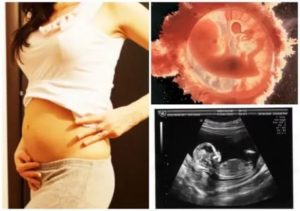

УЗИ первого триместра позволяет уточнить срок беременности, определить размеры, вес, частоту сердцебиения, наличие всех внутренних органов и двигательную активность плода.

Кроме того, ультразвуковое исследование позволяет оценить, правильно ли развивается малыш и даже заподозрить у него наличие генетических аномалий на основе фетометрических данных. Важнейший показатель на этом сроке – размер воротникового пространства.

Также на первом УЗИ определяется место прикрепления плаценты, и в случае ее низкого расположения измеряют расстояние от внутреннего зева матки. Однако это значение может стать больше с ростом матки, так как ее стенки будут растягиваться.

Кроме того, УЗИ позволяет диагностировать исмико-цервикальную недостаточность – состояние, когда мышцы маточного зева слабее, чем требуется для вынашивания беременности.

Если к этому времени беременность протекала без осложнений, то, возможно, на 13 неделе состоится ваше первое УЗИ. Вы сможете видеть, как бьется сердечко маленького, как он двигается, а врачу исследование даст возможность оценить состояние плода и беременности:

- точно установить срок беременности и количество плодов;

- оценить жизненные показатели плода;

- определить наличие/отсутствие тяжелых пороков, несовместимых с жизнью;

- провести скрининговое исследование на определение группы риска женщины относительно хромосомных аномалий у плода (в частности, синдрома Дауна).

Различают ультразвуковое и биохимическое скрининговое исследование. Первый скрининг во время беременности проводится на сроке 11-16 недель, вполне вероятно, что вас направят на УЗИ и сдачу анализов именно на этой неделе.